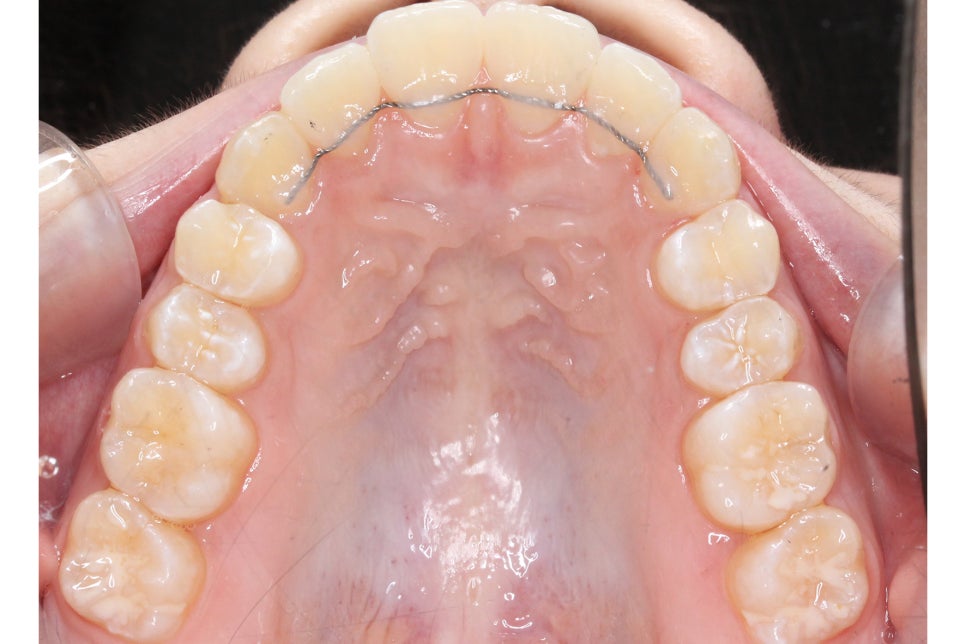

송곳니덧니 교정 전 상악의 치아 배열을 보면

전체적으로 좁고 긴 안모의 모습을 하고 있는데요,

순측으로 뻐드러져 있는 견치를 바른 각도로

조정하기 위해서 구치부 치아를 이동시켜

공간을 확보해야 할 것으로 보입니다.

아랫니의 경우 전치부의 총생이 심하고

삐뚤어진 부분에 치석과 치태가

쌓일 위험이 있기 때문에

바른 치아 배열을 중점적으로

비발치 클리피씨교정을 진행하였습니다.